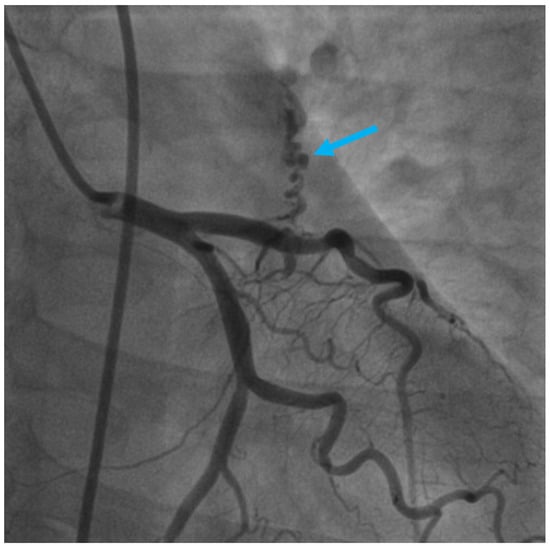

Figure 2. Axial sections of coronary CTA acquisitions—entitled “A picture is worth a thousand words”. show an anomalous tortuous vascular connection with drainage situs in the anterior surface of the pulmonary trunk, fully illustrating diffusion of the resulting contrast blush within the pulmonary trunk, also known as the contrast shunt sign, in a relatively less-opacified pulmonary trunk (pink arrow).